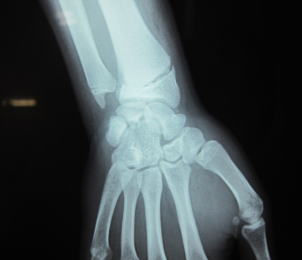

骨が折れる・ひびが入る(腫れがひどく内出血を伴う 関節が外れる(顎・肩・小児の肘等) くじる・捻って受傷する。靭帯・筋肉を痛める 打ち身・物にあたる・ぶつける 肉離れ・筋肉損傷 当院では超音波観察装置を導入しています。 ◎骨・筋・神経・腱の損傷・血腫を観る事ができます。 ◎放射線では無いので、被爆の心配することなく、 人体に無害で、高血圧・妊婦の方にも安心・安全に何度でも観察することができます。 ![]() ![]() |